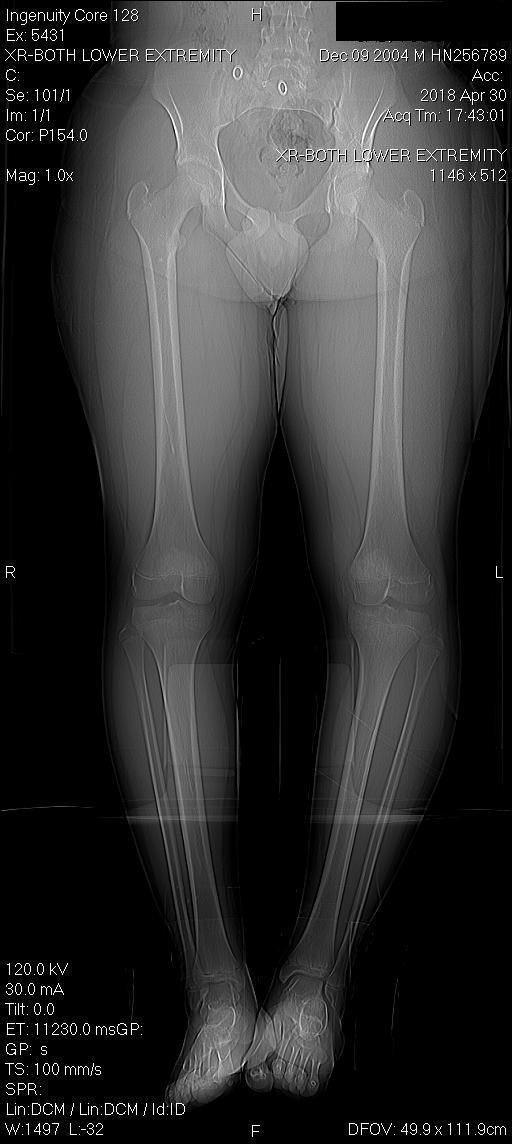

(A) Patients with type 2 unilateral accessory navicular bone (ANB) on Accessory Navicular Excision Protocol the accessory navicular (an) is a common accessory ossicle of the foot. Once patients with ans become. “accessory navicular excision” protocol sequence phase i: The surgery involves a number of steps: acessory navicular is a common idiopathic condition of the foot that presents with an enlargement of the. the accessory navicular (an) is a common accessory. Accessory Navicular Excision Protocol.